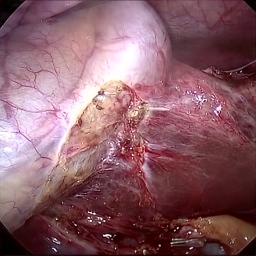

Refer to caption Refer to caption Refer to caption Refer to caption Refer to caption Refer to caption

Refer to caption (a) Input Refer to caption (b) case1 Refer to caption (c) case2 Refer to caption (d) case3 Refer to caption (e) Ours Refer to caption (f) Target

Figure 4: Ablation comparisons sampled from the DesmokeData and LSD3K datasets. The first two rows are from DesmokeData and the last two rows are from LSD3K. (settings: case1 = ADA+CrossGating, case2 = DHA+CrossGating, case3 = DHA+ADA).

IV-D Ablation Studies

To validate the effectiveness and individual contributions of the core components of our proposed RGA-Net, we conducted a series of ablation experiments on the DesmokeData dataset. We systematically analyzed the impact of our key designs: the DHA module, the ADA module, and the Cross-Gating (CG) mechanism for feature fusion. In these studies, we created several variants of our network by removing or replacing one component at a time and evaluated their performance. The quantitative results of these experiments are presented in Table II, and qualitative visual comparisons are shown in Fig. 4.

IV-D1 Effectiveness of the Dual-Stream Hybrid Attention Module

The DHA module is designed to capture both local surgical details and global illumination changes by combining shifted window attention with a frequency-domain processing branch. To ablate its effect, we replaced the DHA modules in the encoder with standard Swin Transformer blocks, thus removing the spectral pathway and the hybrid attention mechanism. As demonstrated in Table II, this variant experienced a significant drop in performance. This decline highlights the importance of integrating frequency-domain information, which is crucial for handling the complex light scattering caused by surgical smoke and restoring high-frequency textural details. The results confirm that the dual-stream approach provides a richer feature representation than spatial attention alone.

IV-D2 Effectiveness of the Axis-Decomposed Attention Module

We then investigated the contribution of the ADA module, which is employed in the decoder and latent space to efficiently process multi-scale features. We created a variant where the ADA modules were substituted with a more conventional self-attention mechanism without the block and grid axis decomposition. The results in Table II show a clear degradation in performance for this variant compared to the full model. This outcome validates that factorizing attention along two distinct axes allows the model to capture both fine-grained local patterns and long-range spatial dependencies more effectively and efficiently. The ADA module’s design provides a powerful yet computationally manageable way to model complex feature relationships during the reconstruction phase.

IV-D3 Effectiveness of the Cross-Gating Mechanism

Finally, we analyzed the efficacy of the cross-gating mechanism used for multi-scale feature fusion between the encoder and decoder. We replaced our CG blocks with a standard skip-connection method, specifically simple concatenation followed by a convolutional layer, as is common in many U-Net-based architectures. As shown in Table II, this change resulted in a substantial performance decrease. This finding underscores the superiority of the bidirectional feature modulation offered by our CG mechanism. Unlike simple fusion, cross-gating allows the encoder and decoder pathways to selectively amplify relevant features and suppress irrelevant information from each other, leading to a more refined and effective integration of multi-scale context, which is vital for high-quality image reconstruction.

In conclusion, the ablation studies comprehensively demonstrate that each of our proposed components—DHA, ADA, and CG—is integral to the overall performance of RGA-Net. The full model consistently outperforms all ablated variants, proving the synergistic benefits of our architectural design for the challenging task of surgical smoke removal.